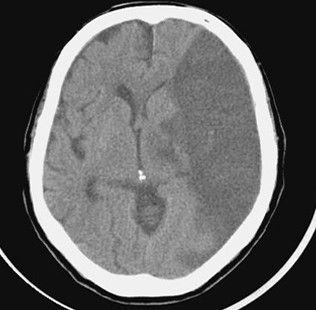

뇌의 혈관이 막혀 해당 영역의 뇌 일부가 죽는 상태입니다. 뇌혈전증과 뇌색전증이 있습니다. 심한 협착으로 인해 뇌로 가는 혈관이 완전히 막히거나 혈류가 현저히 감소하면 뇌 조직의 이 부분이 죽고 결국 녹습니다. 뇌연화증은 뇌세포가 죽어 부드러워지는 현상이고, 뇌성마비는 뇌경색으로 인해 뇌세포가 죽어가는 현상이다. 요약하자면 뇌혈관이 막혀 눈앞의 뇌조직이 괴사하는 질환이다.

뇌혈관이 막혀 뇌의 일부가 파괴되는 질환이다. 심장병이나 동맥 경화로 인해 발생할 수 있으며 이는 60세 이상의 사람들에게 더 흔합니다. 고혈압, 고지혈증, 당뇨병이 있는 사람들은 동반 증상을 경험할 수 있지만 날씨가 추울 때 노인들에게 더 흔합니다. 뇌의 특정 부위에 흔히 발생하며 한쪽 팔과 한쪽 다리의 마비가 뇌경색의 대표적인 증상이다.